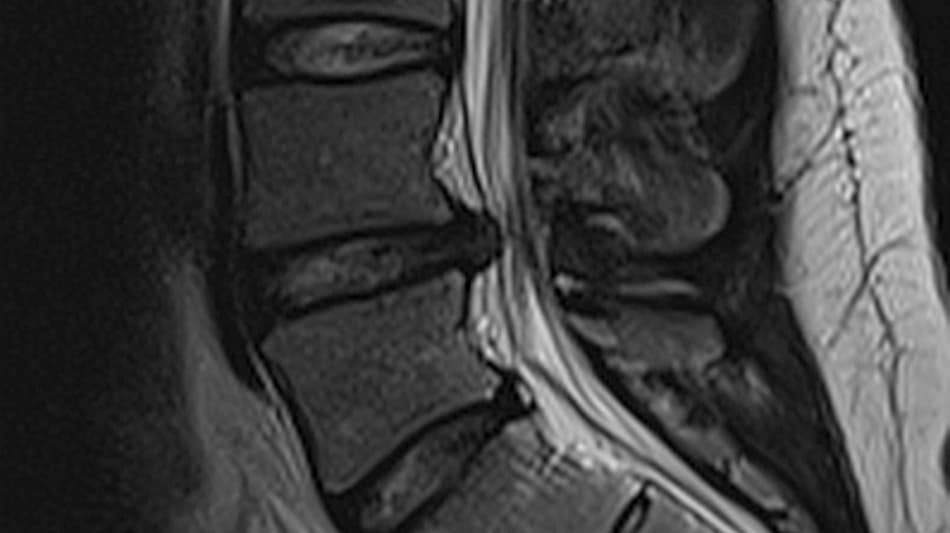

I forbindelse med udredning af lændesmerter er MR-skanning den mest anvendte billeddiagnostiske modalitet [1], da den bedre visualiserer relevante anatomiske detaljer som diskus og nerver end f.eks. røntgenundersøgelse og CT, som har bedre fremstilling af knoglerne (Figur 1). Brugen af MR-skanning har været støt stigende i det seneste årti, og i 2021 blev der foretaget ca. 85.000 MR-skanninger af lænden, hvilket er en stigning på over 20% siden 2013 [1]. Tendensen ses, på trods af at der i kliniske guidelines frarådes rutinemæssig brug af MR-skanning i diagnosticeringen af lændesmerter [2]. Størstedelen af patienter med nyopståede lændesmerter oplever en spontan bedring efter kort tid [3]. Der er ikke evidens for, at MR-skanning har positiv indflydelse på patientrapporterede effektmål såsom smerte eller funktion [4], og en MR-skanning vil derfor som regel ikke ændre hverken behandling eller prognose.